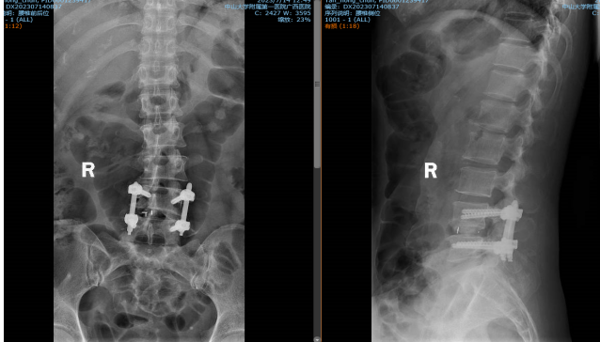

▲④术后X线片

术后第一天,医生为谭阿姨伤口换药并为他进行了腰椎X线及CT复查,显示手术后内固定植入物固定良好,椎间融合器放置在位,下肢麻木及疼痛症状明显好转。经过一系列的康复锻炼,谭阿姨术后第二天下床行走,术后5天办理出院。